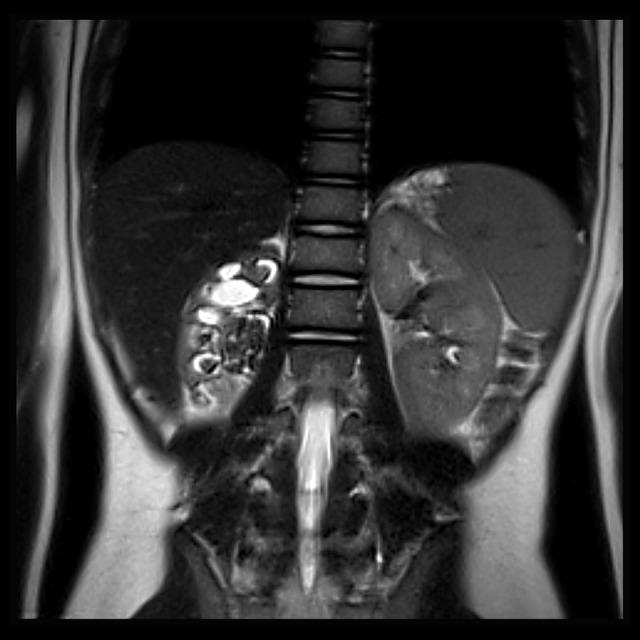

BACKGROUND Xanthogranulomatous pyelonephritis (XP) is an extremely rare, severe, atypical form of chronic renal parenchymal inflammation accompanied by hydronephrosis and/or urolithiasis. The pathomechanism of XP is not yet fully understood. Microscopically, XP is indicated by the presence of multinucleated giant cells and lipid-laden macrophages, as well as inflammatory infiltration and intensive renal fibrosis. The lipid accumulation in kidney parenchyma may be secondary to the altered flow of low-density lipoprotein (LDL)-derived cholesterol particles inside the affected cells. Physiologically, the process of LDL-derived cholesterol transport from lysosomes to the sites of its esterification is dependent on vimentin, which is a molecule comprising the cytoskeleton in mesenchymal cells. CASE REPORT A 7-year old girl was hospitalized because of the finding of unexplained kidney lesions on an abdominal ultrasound examination (an enlarged and deformed collecting system of the right kidney with hyperechogenic, solid, staghorn lesions in the calyces). Three months earlier, the patient had experienced recurrent urinary tract infection. Based on the subsequent laboratory and imaging diagnostics, the final diagnosis of XP was established and the girl was qualified for right-sided nephrectomy Microscopic examination revealed numerous foci of granuloma formations with no evident exponents of dysplastic or neoplastic abnormalities. Significant CD68-positive cell infiltrations and scattered foam cells arranging the numerous foci of granuloma inflammation were noticed. Renal parenchyma, adjacent to granuloma lesions, presented a vimentin expression. CONCLUSIONS Vimentin expression in XP may confirm a focal character of chronic granuloma formation and may suggest the complexity of XP pathogenesis involving not only macrophage and fibroblast activation but also local lipid deregulation and fibrosis.

背景 黄色肉芽肿性肾盂肾炎(XP)是一种极为罕见、严重的慢性肾实质炎症的非典型形式,伴有肾积水和/或尿路结石。XP的发病机制尚未完全明确。在显微镜下,XP表现为多核巨细胞、充满脂质的巨噬细胞的存在,以及炎症浸润和严重的肾纤维化。肾实质中的脂质蓄积可能继发于受累细胞内低密度脂蛋白(LDL)衍生的胆固醇颗粒流动改变。生理上,LDL衍生的胆固醇从溶酶体转运至其酯化部位的过程依赖于波形蛋白,波形蛋白是一种构成间充质细胞细胞骨架的分子。病例报告 一名7岁女孩因腹部超声检查发现不明原因的肾脏病变(右肾集合系统增大、变形,肾盏内有高回声实性鹿角状病变)而住院。3个月前,该患者曾反复发生尿路感染。基于后续的实验室和影像学诊断,最终确诊为XP,该女孩符合右侧肾切除术条件。显微镜检查显示有大量肉芽肿形成灶,未见发育异常或肿瘤异常的明显表现。注意到显著的CD68阳性细胞浸润以及散在的泡沫细胞排列成众多肉芽肿炎症灶。与肉芽肿病变相邻的肾实质呈现波形蛋白表达。结论 XP中的波形蛋白表达可能证实慢性肉芽肿形成的局灶性特征,并可能提示XP发病机制的复杂性,不仅涉及巨噬细胞和成纤维细胞的激活,还涉及局部脂质失调和纤维化。